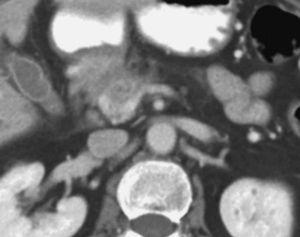

Aunque algunos autores no han observado diferencias significativas en cuanto al rendimiento de la TC helicoidal monofásica y bifásica en la detección y estadificación del cáncer de páncreas13, otros autores19,32, en series más largas incluyendo un mayor número de pacientes con tumores resecables, han aseverado el rendimiento de la TC helicoidal bifásica en la predicción de la resecabilidad del cáncer de páncreas, presentando valores predictivos para la resecabilidad tumoral entre 73,5% y 77% y valores de precisión diagnóstica entre 77% y 83%. Revisando específicamente los signos TC de infiltración vascular mediante TC helicoidal bifásica, Lu et al33, utilizando un sistema de gradación basado en la contigüidad del tumor con cada una de las estructuras vasculares (venas porta y mesentérica superior, o arterias hepática, mesentérica superior y tronco celíaco), presentaron un valor predictivo positivo del 95% y un valor predictivo negativo para la irresecabilidad neoplásica del 93% cuando consideraban infiltración vascular una contigüidad del tumor que excedía el 50% de la circunferencia del vaso en cuestión (fig. 4). A este mismo respecto Phoa et al34 describen como criterios de TC más fiables de invasión venosa la estenosis e irregularidad de la vena porta o la vena mesentérica superior, así como una contigüidad circunferencial del tumor con la vena porta superior a 90º (fig. 5). Los autores concluyen que la mejor combinación de criterios de TC fue la concavidad tumoral con afectación circunferencial vascular, con lo que presentan una sensibilidad del 61% y especificidad del 90%. Hough et al35 describieron el signo de la lágrima de la vena mesentérica superior, que consiste en una deformidad de la morfología redondeada de la vena adyacente al tumor en las secciones axiales, como indicativo de invasión venosa (fig. 6). Añadiendo este signo a los ya descritos de invasión venosa, consiguen aumentar la sensibilidad (60-91%) y el rendimiento diagnóstico de la TC (79-95%) sin modificar significativamente la especificidad (100-98%). No obstante, estos sistemas de gradación para el diagnóstico de la invasión vascular peripancreática tienen el inconveniente de la subjetividad a la que está sometida su lectura. Los casos extremos no presentan problemas de interpretación, pero la valoración del tumor rodeando al vaso alrededor de 90º de su circunferencia puede ser difícil, dado que además pueden existir bandas de infiltración de la grasa peripancreática que pueden rodear parcialmente un vaso o incluso continuarse sin plano graso de separación con el tejido tumoral. Estas bandas pueden representar cambios edematosos o inflamatorios locales (fig. 7). En este sentido, Valls et al19,36 presentan únicamente un 25% de valor predictivo positivo para la irresecabilidad tumoral para estas bandas perivasculares. Además se ha descrito la notoria variabilidad interobservador en función de su experiencia, que llega a alcanzar una diferencia de sensibilidad de hasta un 20% entre revisores experimentados y noveles14.

Fig. 6.--Estudio de tomografía computarizada con contraste endovenoso en fase venosa portal. Infiltración vascular de la vena mesentérica superior. Signo de la lágrima: deformidad focal de la morfología de la vena en contigüidad con el tumor.